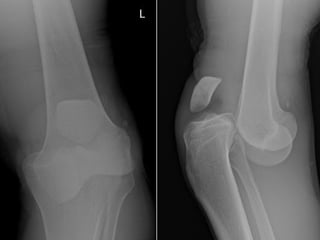

4. Dislocation

“dislocation is an injury in

which the ends of your

bones are forced from their

normal positions. The

cause is usually trauma

resulting from a fall, an

auto accident, or a collision

during contact or high-

speed sports.

Dislocation usually involves

the body's larger joints. In

adults, the most common

site of the injury is the

shoulder. In children, it's

the elbow.

Your thumb and fingers

also are vulnerable if

forcibly bent the wrong

way.The injury will

temporarily deform and

immobilize your joint and

may result in sudden and

severe pain and swelling.

A dislocation requires

prompt medical

attention to return

your bones to their

proper positions”.